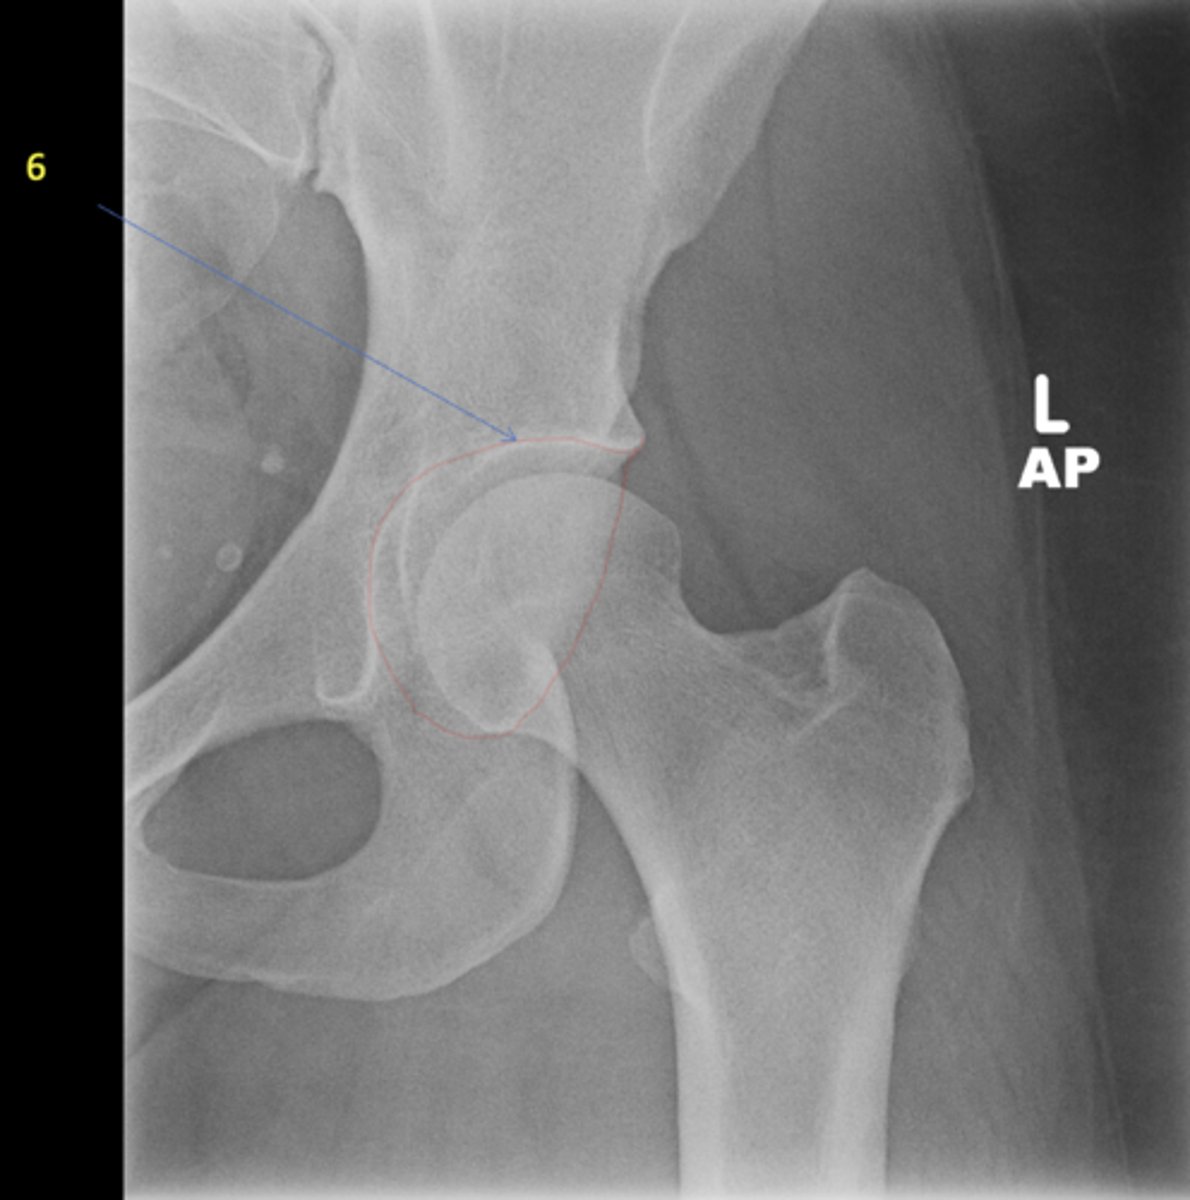

<p>View?</p>

2

New cards

Right lesser trochanter

ID 2

<p>ID 2</p>

3

Left greater trochanter

ID 3

<p>ID 3</p>

4

Right iliac crest

ID 4

<p>ID 4</p>

5

Right iliac fossa

ID 5

<p>ID 5</p>

6

Left anterior superior iliac spine

ID 6

<p>ID 6</p>